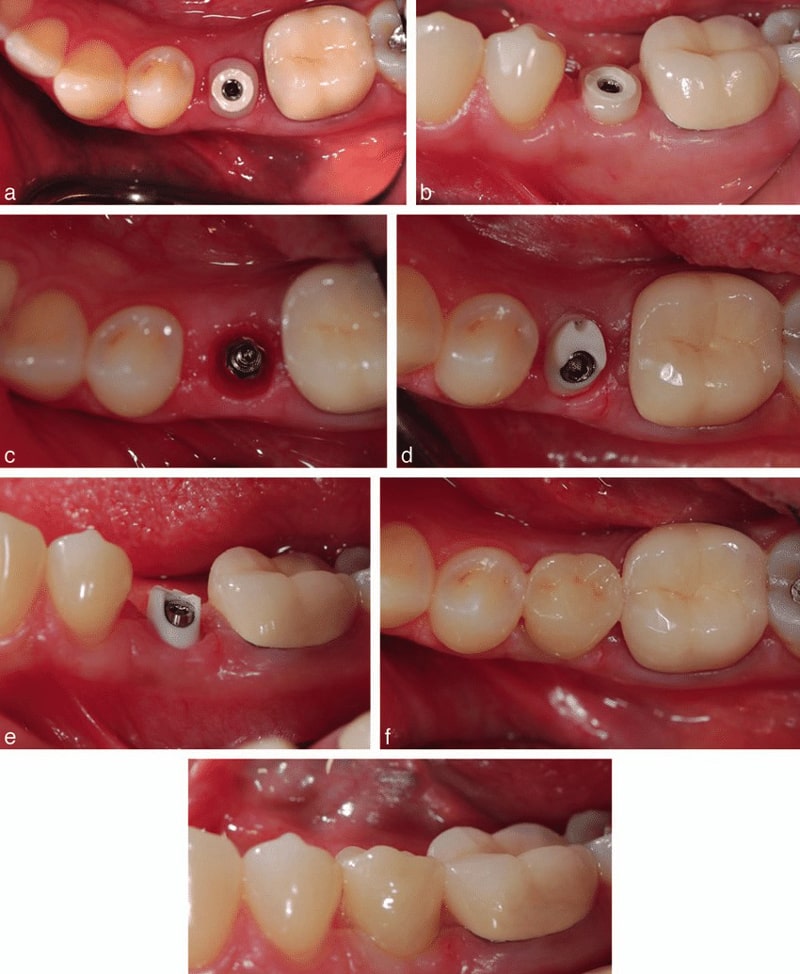

ایمپلنت دندان زمانی بهترین گزینه محسوب می شود که دندان تان به طور کامل از بین رفته باشد؛ یعنی هم تاج و هم ریشه آسیب دیده و قابل ترمیم نیستند؛ در چنین شرایطی، دیگه روش هایی مثل پست و روکش پاسخگو نیستند، چراکه ریشه ای برای نگهداری وجود ندارد.

ایمپلنت یک جایگزین عالی و خیلی مشابه به دندان های طبیعی است. اگر چند دندان از دست داده اید یا می خواهید از دندان مصنوعی متحرک خلاص شوید، ایمپلنت می تواند جایگزینی عالی برایتان باشد.

برای کسانی که تراکم استخوان فک خوبی داشته و به سلامت لثه هایشان اهمیت می دهند، ایمپلنت یک انتخاب مطمئن با طول عمر بالا است؛ همچنین ایمپلنت برای افرادی که می خواهند زیبایی لبخندشان را بازگردانند یا از لق شدن دندان مصنوعی خسته شده اند، گزینه ای بی نظیر است. البته باید توجه داشت که این روش نیاز به صبر، هزینه نسبتاً بالا و رعایت دقیق بهداشت دهان و دندان دارد تا ایمپلنت سالم باقی بماند.

انجام ایمپلنت چقدر طول می کشد؟

بهطور متوسط:

- جراحی کاشت پایه: 1 جلسه

- جوش خوردن پایه با استخوان: 2 تا ۶ ماه

- نصب اباتمنت و روکش: 1 تا ۲ جلسه

در مجموع: بین ۳ تا ۶ ماه طول میکشد.

دوره نقاهت ایمپلنت چقدر است؟

- ۳ تا ۷ روز درد و تورم طبیعی است.

- بعد از یک هفته، می توان کارهای عادی مثل غذا خوردن را با ایمپلنت انجام داد.

نکته: جوش خوردن کامل استخوان، حدود ۲ تا ۶ ماه زمان می برد.

اگر ریشه دندان به طور کامل از بین رفته باشد، کشیدن دندان و کاشت ایمپلنت بهترین گزینه است، چرا که پایه آن، درون استخوان فک قرار گرفته و عملکردی مشابه دندان طبیعی دارد؛ اما اگر ریشه هنوز سالم است و فقط ساختار دندان، آسیب جدی دیده است، بهترین گزینه استفاده از پست یا روکش دندان است تا با کاشت پایه فلزی و نصب تاج، ساختار دندان را تقویت کرده و دندان طبیعی را حفظ کرد.

اگر دندان دچار مشکل شده باشد، برای درمان آن باید به دندان پزشک مراجعه کرد؛ دندان پزشک ابتدا سعی می کند تا با پر کردن دندان یا عصب کشی، دندان را درمان کرده تا دندان طبیعی حفظ شود؛ ولی اگر کار از این کار گذشته بود، باید دندان کشیده شود؛ پس از کشیدن دندان، باید جای آن را با گزینه دیگری پر کرد که این کار را می توان با انواع ایمپلنت انجام داد. به صورت میانگین، کاشت ایمپلنت در سال ۱۴۰۴، هزینه ای در حدود ۸.۵ تا ۶۰ میلیون تومان در پی دارد.